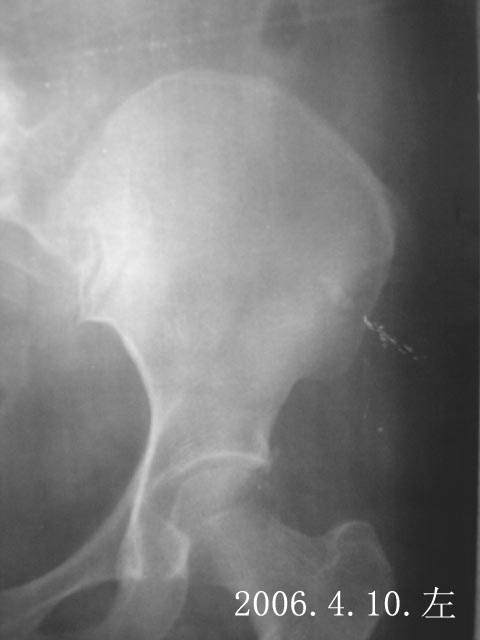

患者女性,51岁。左髂嵴部疼痛2月余,局部无红肿,髂前上嵴部压痛与扣打痛(+),但触不到明显肿块。请各位专家会诊。

图象不是太清楚,看上去应是骨软骨瘤,

所提供的图片不能说明该处有病变如骨化性肌炎或骨软骨瘤等,建议多角度观察应可以明确有无病变,当然做ct更加明确还可以观察软组织改变;如果确有病变,还应问问病史(局部有无外伤史),除外骨化性肌炎或血肿机化。